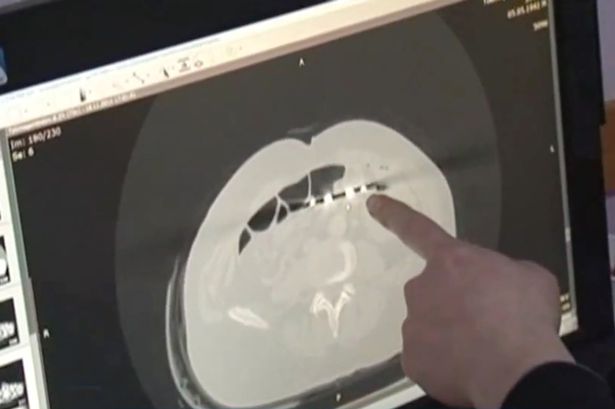

Dopo essersi rassegnato a provare dolore perennemente, Karp da un mese aveva cominciato a dimagrire perdendo anche l’appetito. Ha così pensato di recarsi all’ospedale per una visita e lì, grazie ai raggi x, hanno scoperto l’arcano.

Le forbici che aveva nello stomaco era quelle utilizzato da chirurghi e lunghe quasi 20 centimetri. I medici hanno raccontato di non aver mai visto niente del genere.